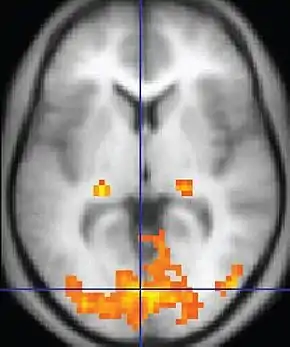

Functional MRI (fMRI)Blood-oxygen-level dependent imagingBOLDChanges in oxygen saturation-dependent magnetism of hemoglobin reflects tissue activity.[78] Localizing brain activity from performing an assigned task (e.g. talking, moving fingers) before surgery, also used in research of cognition.[79]